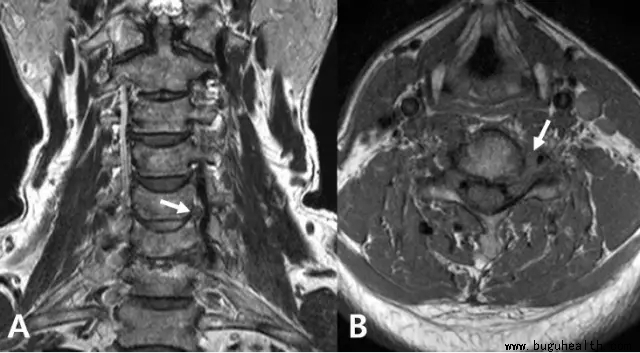

下图,MRI显示左侧椎动脉受压(白色箭头):